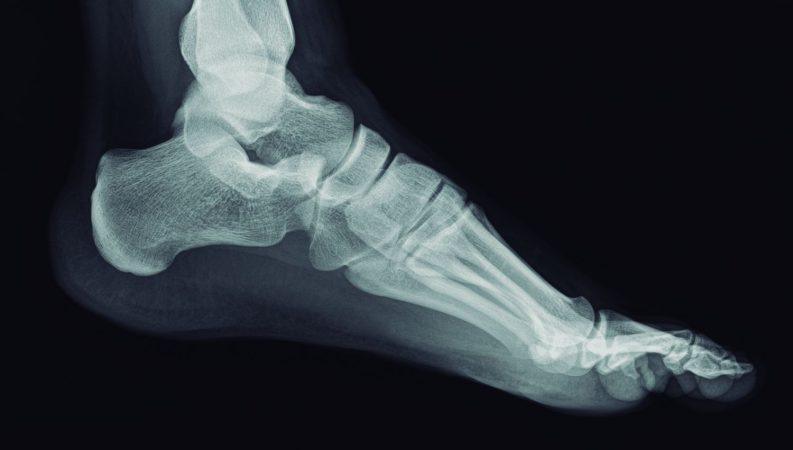

Cada jornada, cientos de radiografías pasan por sus manos, y detrás de cada una hay un relato: fracturas, accidentes domésticos o episodios que rozan lo inverosímil. En su trabajo, lo técnico se mezcla con lo humano, y la precisión científica con la empatía más pura.

Jonathan lleva más de siete años ejerciendo como técnico de radiología en un hospital público del norte francés. Allí, las radiografías se convierten en una ventana al cuerpo humano, pero también en un espejo de la sociedad. Desde lesiones deportivas hasta accidentes de tráfico, cada imagen habla del comportamiento, los hábitos y los descuidos de la vida moderna.

No todas las radiografías muestran historias insólitas. Muchas reflejan dolencias cotidianas, como fracturas de cadera en personas mayores, comunes en regiones con poco sol y déficit de vitamina D. En estos casos, el papel del técnico se vuelve esencial para detectar con rapidez lesiones graves y facilitar la intervención médica inmediata.